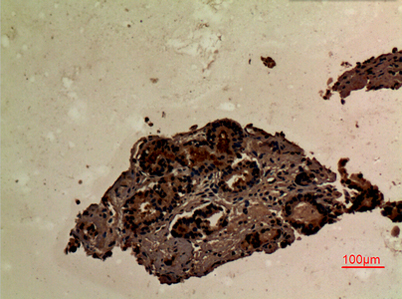

Product name: SLP-76 rabbit pAb

Dilutions: Western Blot: 1/500 - 1/2000. IHC-p: 1:100-300 ELISA: 1/10000. Not yet tested in other applications.